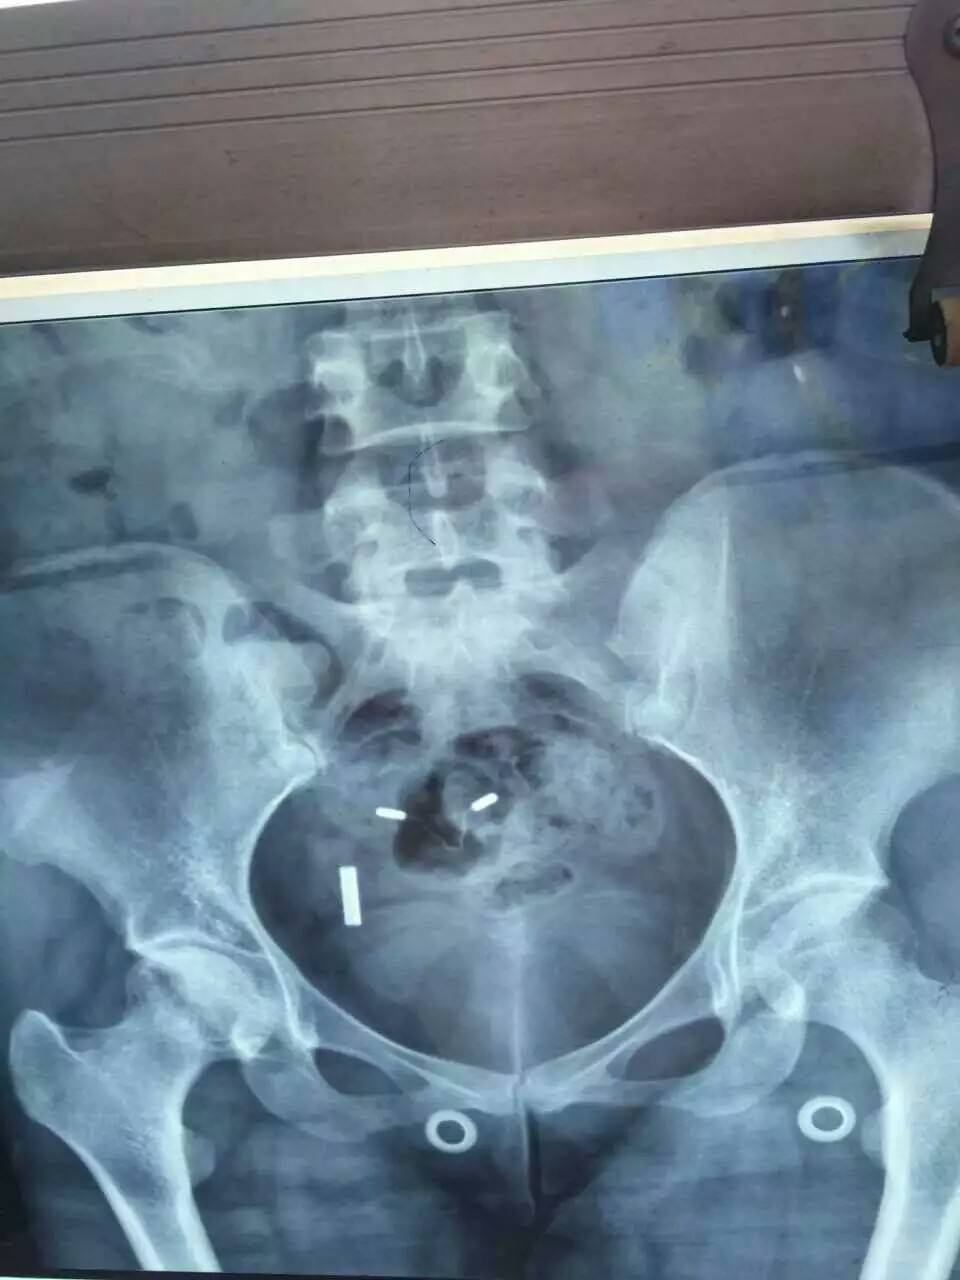

前几天复查一切都还好,就是腿好像比上次严重点,这半年太不注意了走路太多。有会看片子的吗?帮我看看骨质怎么样?前两张是刚拍的,后面一张是去年的。

我的片子比你的略强一些,去年拿去北京想做置换,医生说看片子可做可不做,主要是看病人活动是否受限